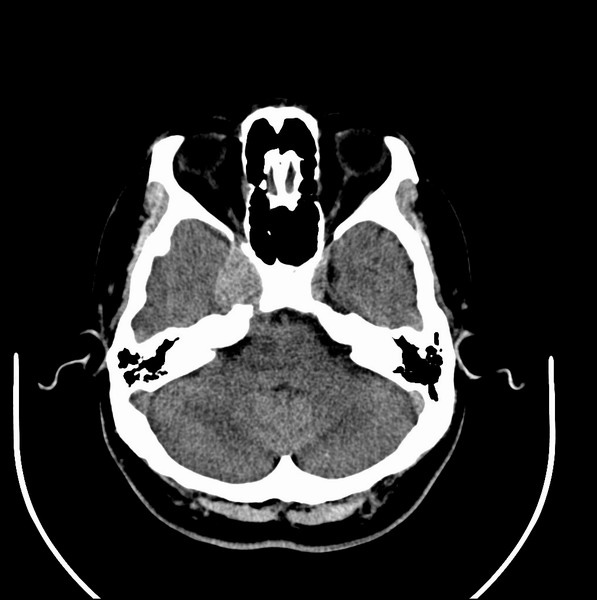

扫描示鼻咽腔不对称,中度狭窄,右侧咽隐窝消失,局部软组织肿块,鼻咽右侧壁增厚形成肿块,突入鼻咽腔,肿块平扫呈等密度,肿块向深部侵润,右侧翼内外肌受侵,右侧咽旁间隙变窄;向后生长,头长肌界线欠清,向后上生长侵犯同侧颈动脉鞘区。双侧海绵窦增宽,内见软组织影与鼻咽部肿块相连。考虑鼻咽癌。鼻咽癌主要是放射治疗,且效果较好;到当地有治疗设备较大医院治疗即可。

典型鼻咽癌侵犯右侧海绵窦(对放疗敏感)

还是先确诊,如果是鼻咽癌,一般行放射治疗;这例患者我首先考虑鼻咽癌